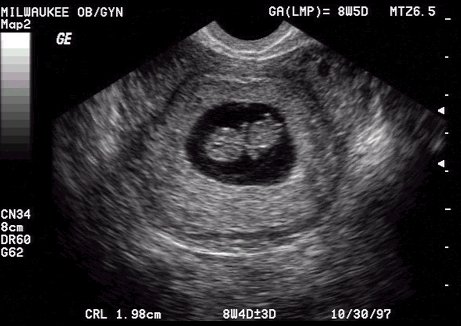

3d ultrasound coachella valley. This 3d ultrasound and 4d ultrasound provider directory features 3d 4d ultrasound centers in the us and canada. It is our goal to make this the most comprehensive directory of 3d4d ultrasound centers. 3d 4d hd ultrasound locations. Abdominal ultrasound to evaluate the gallbladder liver and other abdominal organs.

We came into existence to provide amazing 3d 4d hd live ultrasounds to the community and create a positive bonding experience between expectant family and baby to be. Heavenly 3d4d imaging provides the following services ultrasounds3d4d imaging services digital imaging. Ultrasound is very useful in studying both arteries and veins throughout your neck chest abdomen and extremities. Be sure to purchase additional 3d ultrasound photos and 4d ultrasound video dvds so you can share with family and friends.

In 2003 we started with just two ultrasound centers listed. 3d 4d ultrasound by 4d special delivery offers expecting families an opportunity of a lifetime a bonding experience with your baby in the womb with a 3d 4d ultrasound or hd live ultrasound session close to coachella valley california. 3d ultrasound photos and 4d ultrasound videos allow the whole family to bond with your baby. Please follow these tips from the california department of health and human services.

Extra 4d ultrasound videos. Coachella ultrasound is a professional imaging facility located in the coachella valley specializing in 3d4dhd ultrasound services. Here are some examples of ultrasound study types and their purpose.